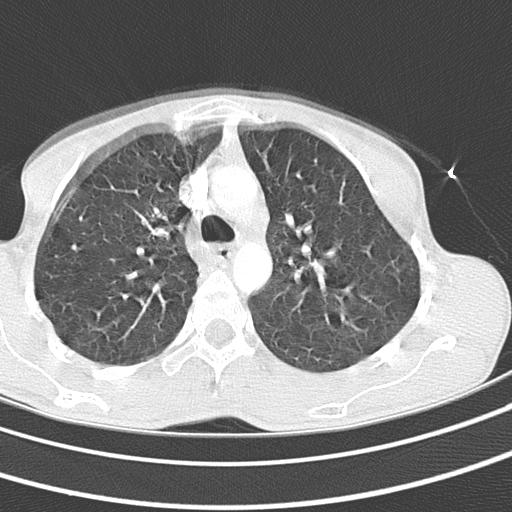

Ik zal er ineens de enige foto die ik heb opsmijten.

Volgens mij is dit toch wel een serieuze + achter de rekening voor hypochondrie/hysterie.

Bijgevoegde miniaturen

Klik op de afbeelding voor een grotere versie

Naam:  00016908.JPG‎

Bekeken: 175

Grootte:  42,4 KB

ID: 83311

Lijkt me toch wel meer dan scherp genoeg.